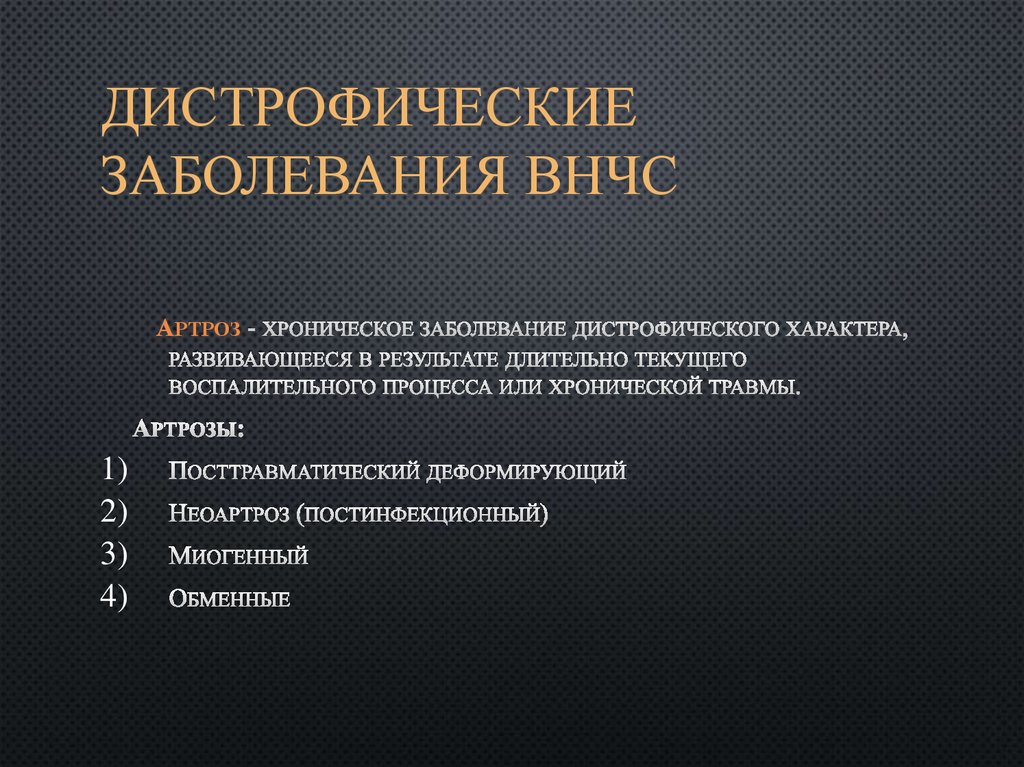

Дистрофические заболевания внчс презентация - 89 фото